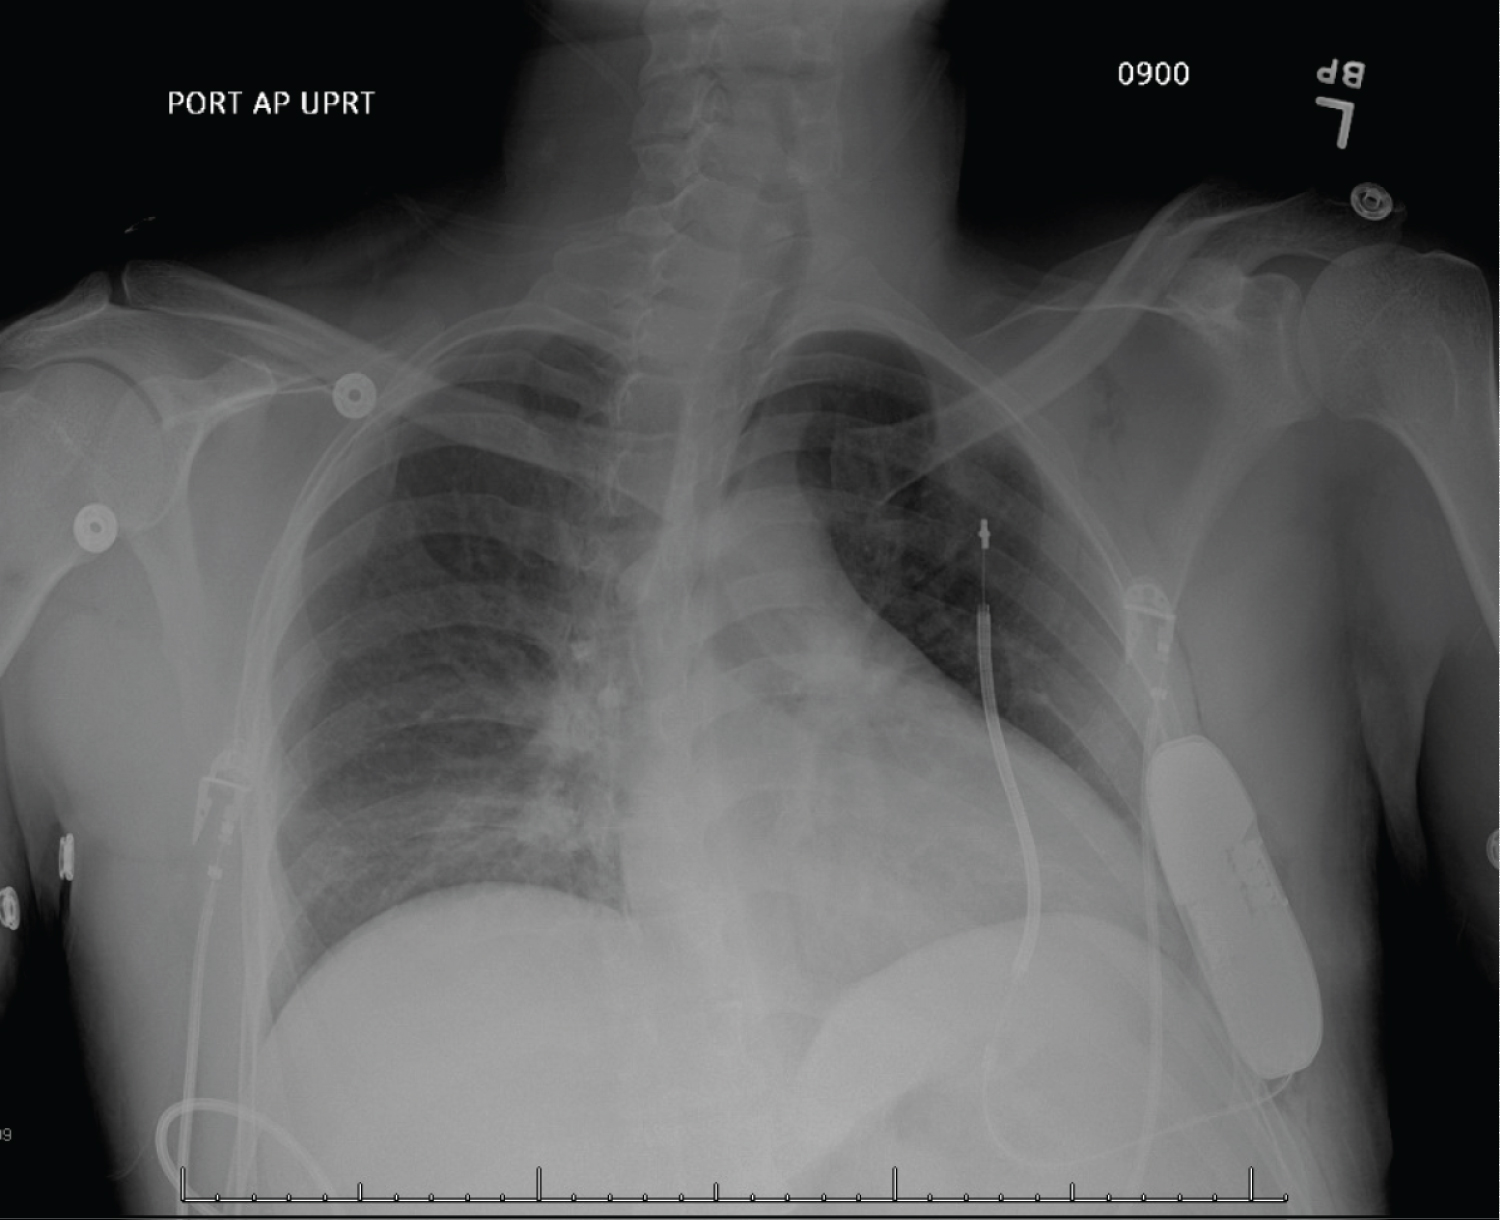

A 31-year-old male with no significant past medical history presents after a witnessed syncopal episode. He denied any pre or post syncopal symptoms of chest pain, palpitations, fevers, nausea, loss of bowel or bladder control or tongue biting. He does not take any medications and denied any family history of sudden cardiac death. His physical exam and laboratory workup were unremarkable. His ECG showed sinus rhythm with coved ST segment elevation and T wave inversions in leads V1 and V2 consistent with type 1 Brugada pattern (Figure 1). His echocardiogram was unremarkable with normal chamber size, no hypertrophy or valvular disease and a left ventricular ejection fraction of 60%. He was evaluated by general cardiology and electrophysiology and due to the concern for Brugada associated ventricular tachyarrhythmias as the culprit for his syncopal event, the placement of a defibrillator was recommended. After lengthy discussions with the patient about the different types of defibrillators, he elected to have a subcutaneous defibrillator (S-ICD) due to its cosmetic advantage, lack of vascular injury risk and low systemic infection risk (Figure 2). Unfortunately, after placement of his S-ICD, the patient had another syncopal episode associated with dizziness while he was in the hospital. The episode was documented on the telemetry monitor and revealed a 12 second sinus arrest (Figure 3A). The patient received brief CPR before regaining consciousness. Continuous telemetry monitoring revealed multiple episodes of sinus pauses of different durations at different times (Figure 3B). Multiple differential diagnoses were entertained including sinus node dysfunction in the setting of Brugada vs. vasovagal syncope. Due to concerns of recurrent episodes, the patient was presented with different management options including the placement of a pacemaker or a dual chamber ICD and the future removal of the subcutaneous ICD. He deferred further procedures and elected to pursue outpatient cardiac event monitoring. He was scheduled to follow up in clinic with recommendation to obtain an outpatient cardiac MRI to rule out infiltrative diseases. He had a few more episodes of sinus pause documented and Mobitz 1 AV block on his event monitor which he reported were not associated with any syncopal events (Figure 4).

Figure 2: Chest X-ray status post subcutaneous ICD placement. View Figure 2